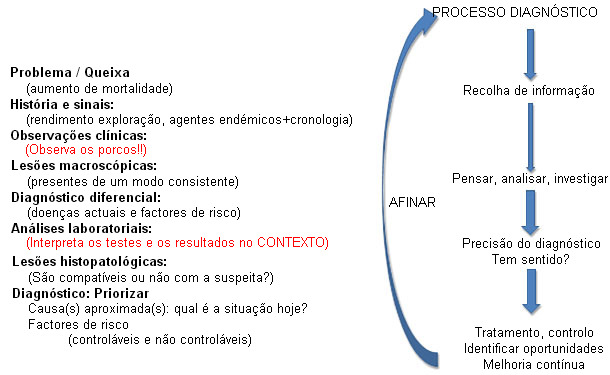

Os testes de diagnóstico são ferramentas que podem ser utilizadas por profissionais com formação e experiência na sua interpretação dentro do contexto do cenário clínico e das evidências macro e microscópicas. A confiança na exactidão de um diagnóstico requer que todos os elementos se "alinhem", ou seja, que sejam precisos e expliquem uma história consistente. As observações ou resultados dos testes que não tenham sentido devem provocar uma imediata reavaliação do processo diagnóstico (figura 3). É um conceito muito simples, mas na prática pode visto por alto. As suposições, as confirmações enviezadas e a consideração superficial das opções diagnósticas podem, e frequentemente levam a, produzir diagnósticos errados.

Figura 3: "Alinhamento" diagnóstico: Toda a informação deve ter sentido.